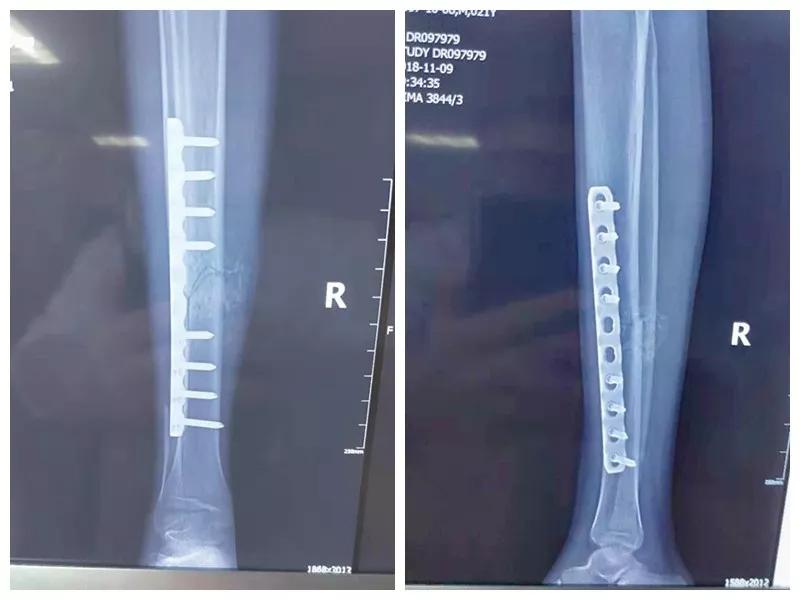

近日,在市中心医院骨二科及血研所、输血科等院内多学科联合协作下,成功为一例严重血液病复杂陈旧骨折患者施行骨移植内固定手术治疗。

这名21岁的男性患者一个月前因车祸致伤,在当地某三甲医院确诊为右胫腓骨粉碎性骨折,骨折移位明显,建议手术治疗,因既往患严重慢性再生障碍性贫血病史16年,一般状况差,需长期输注血液制品维持三系细胞水平,麻醉及手术风险极高。虽经当地积极内科治疗,患者一般状况仍差,无法耐受手术治疗。患者及家属经多方打听,抱着最后一丝希望来到色花堂 骨二科求治。

骨二科张延平主任接诊后经仔细询问病史,详细阅读近期X线、CT等病历资料,认为患者骨折移位明显,目前骨折无任何愈合迹象,若保守治疗,骨折将无法愈合,后期不能下地活动,严重影响患者生活质量。同时患者合并慢性再障,血常规结果各项指标均极低,围术期发生麻醉意外、大出血、感染等风险极高;而色花堂 作为西安市级最大的三甲综合医院,综合实力深厚,既往相关疾病治疗经验丰富,多次通过多学科诊治为合并复杂内科疾病患者保驾护航,为患者创造手术时机,提高患者生活质量,遂将患者收住院。住院后,立即成立了由张延平主任、杨寅副主任、山卉护士长、梁晨主治医师、刘邦定主治医师、李鑫护师组成的手术治疗小组。经初步检查,患者血常规结果较当地检验结果更差,三系细胞均极低,其中血小板仅为1(正常值为100-300),血红蛋白55g/L。遂立即请血研所李罡灿主任医师会诊,给予升高白细胞、纠正贫血、升高血小板等治疗,经积极治疗患者血常规各项指标均较入院时改善。张延平主任再次组织由血研所李罡灿主任医师、麻醉科崔晓岗主任、感染科付建军主任、药剂科韩小年副主任药师等参加的术前讨论。讨论后一致认为患者目前各项指标虽然较入院时改善,但因其慢性再障病史长,骨髓造血及储备能力极差,围术期发生大出血、伤口感染甚至全身感染等风险仍极高,术中及术后需准备大量血小板防止大出血,同时需高度警惕手术切口、取骨区术后发生感染。为尽快为患者施行手术,治疗小组积极联系输血科为患者备血,并为患者制定了围术期抗感染方案;在色花堂 输血科存血量严重不足的状态时,输血科张养民主任亲自联系市中心血站为患者准备手术中及术后所需的血小板制品。手术小组为患者制定了周密的手术方案及风险预案,10月31日,在麻醉科王永宏副主任医师、手术室高洁、赵耀护师的配合下,为患者施行了右胫骨粉碎性骨折切开复位、髂骨取骨植骨内固定术,手术历时70分钟,安全返回病房。术后患者渗血多,1周内连续每日平均渗血超过100ml,并出现发烧,最高39℃,复查血常规三系细胞较术前再次明显降低。李罡灿主任医师、付建军主任、韩小年副主任药师多次来科会诊,及时调整患者的治疗方案,输血科再次为患者的救治提供了强有力的支援和保障。在山卉护士长带领的护理团队精心护理下,患者未发生压疮等卧床并发症。目前该患者术后恢复良好,已出院进行下一步康复治疗。